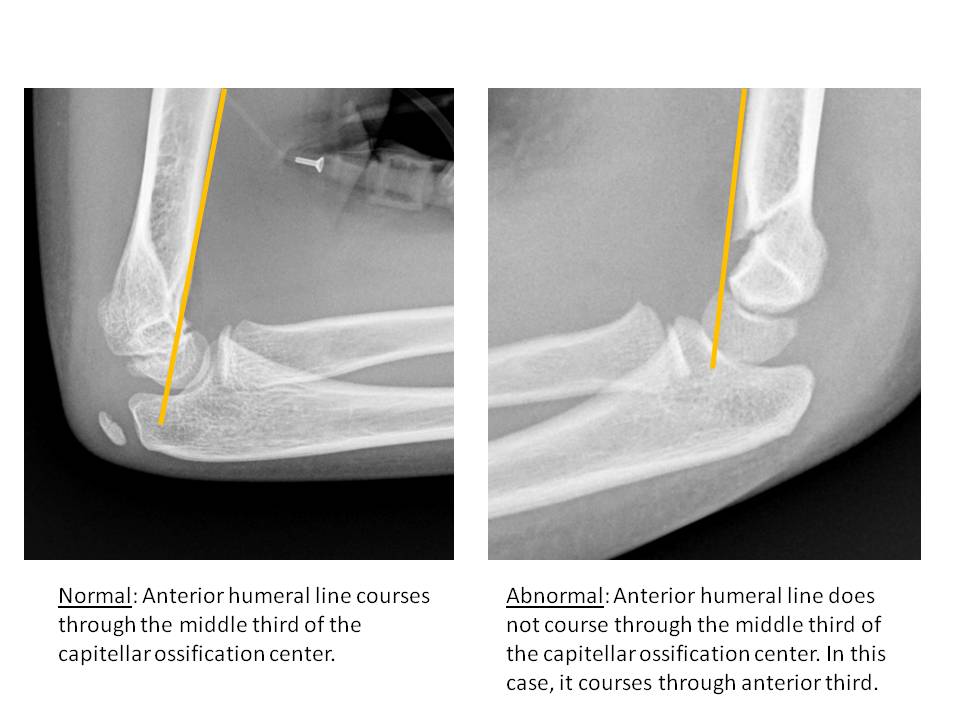

| Alignment | Correct Answer | Your Answer |

|

No | NA |